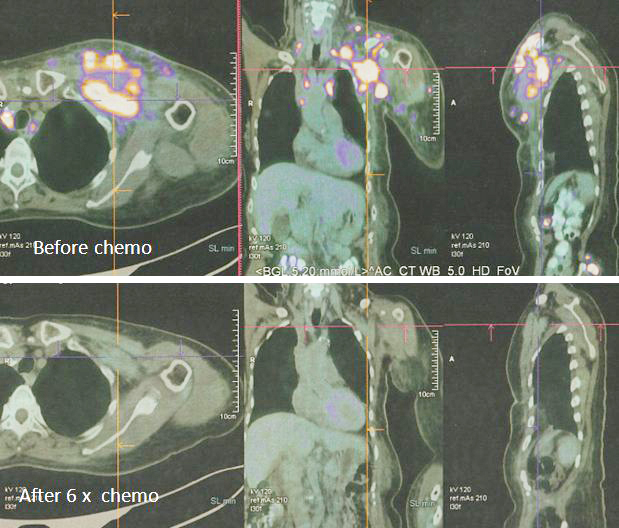

8. PET scan on 14 April 2022 showed good response indeed.

1. Amazing results of chemotherapy. Compare these three pictures –

Left: After surgery Lucy was on alternative therapy, refusing to undergo chemotherapy. The result was extensive metatastasis (middle). Right: Lucy has no choice but to go for chemotherapy. The outcome of 6 cycles of chemotherapy was just fantastic! In my 25 + years dealing with cancer patients, I have never seen such a great outcome of chemotherapy. Salute the oncologist! You rescued her!

In fact, the results were so unbelievable that one is tempted to ask if it is for real and not a fake? My answer is NO, detailed study of the PET scan results below are real! Study the images carefully – those before and after  chemotherapy.